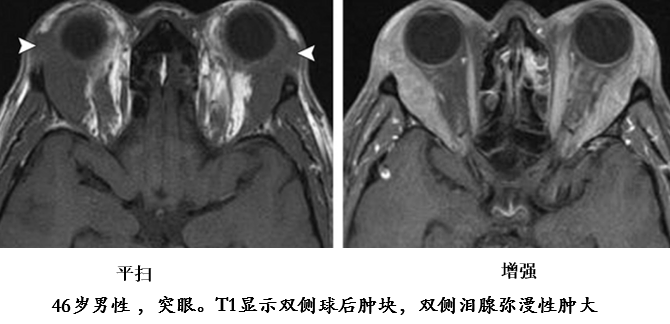

垂体受累

75 岁女性。A 图:双侧泪腺增大,轴位 T2 像显示低信号。B 图冠状位显示左侧眶下神经受累增粗;矢状位 T1 垂体柄增粗, 后叶高信号消失